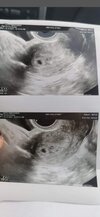

Pecherzyk ciazowy 6mm pusty

Hej kochane. Bylam wczoraj na usg i byl to 5t1d 36dc, nie ma szans ze owulacja byla pozniej niz 14dnia cyklu bo robilam trst owulacyjny i pozniej nie bylo juz przytulanek. Także wiek ciazy jest pewny. Pecherzyk mial tylko 6mm i byl bez cialka zoltego i zarodka. Czy jest jeszcze jakas szansa? Pecherzyk powinien byc juz duzo wiekszy... Czy ktos tez tak mial i dobrze sie skonczylo? Biore progesteron od wczoraj ale nastawiam sie na puste jajo. Dodam ze podczas poczatku cyklu bylam chora i jadlam antybiotyk... Wiwc moze moj organizm sam wyeliminowal slaba komorke..